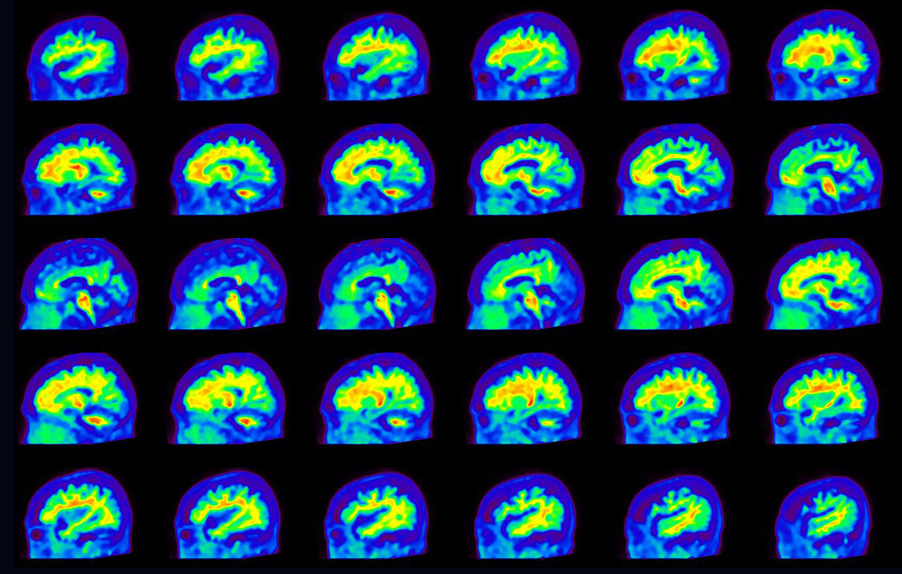

Sagittal